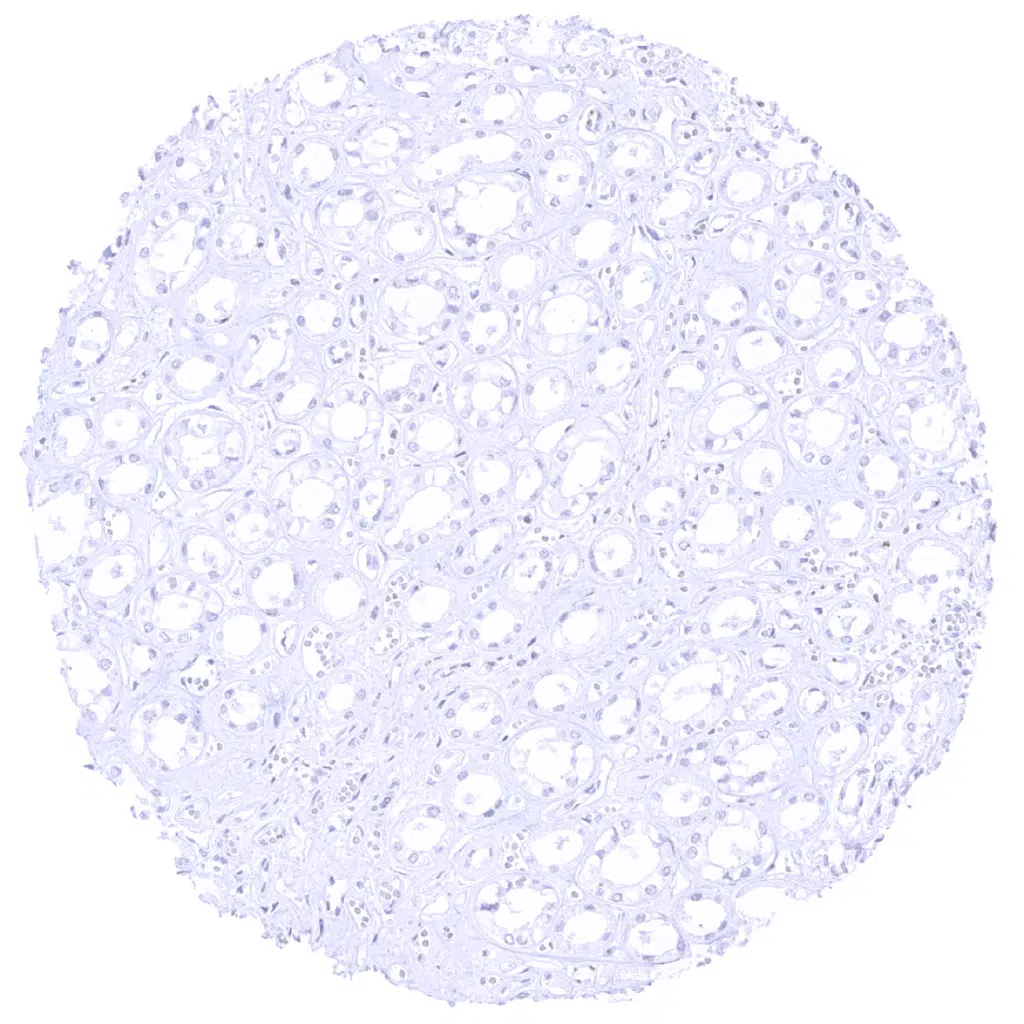

Pancreas – A strong GP2 staining is seen in acinar cells of the pancreas. GP2 staining is lacking in pancreatic ducts.

Pancreas – A strong GP2 staining is seen in acinar cells of the pancreas. The staining is cytoplasmic and membranous and shows a distinct apical predominance.